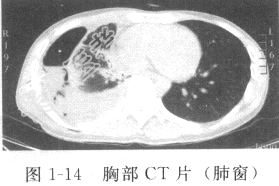

患者男性,28岁,因“反复低热、盗汗2个月,咳嗽、咯血1个月”入院。入院胸部X线片发现右上肺空洞,右下肺胸腔积液。胸部CT平扫示右侧胸腔积液,右下肺炎症(图1-13、图1-14)。结核菌素(PPD)试验(++)。查体:营养中等,精神倦怠,体温38.2℃,右下肺呼吸音消失,叩诊呈浊音。既往有卡介苗接种史,否认结核患者接触史。